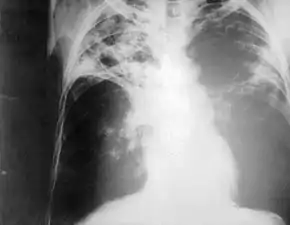

Chest radiography showing advanced bilateral pulmonary tuberculosis. Source: CDC